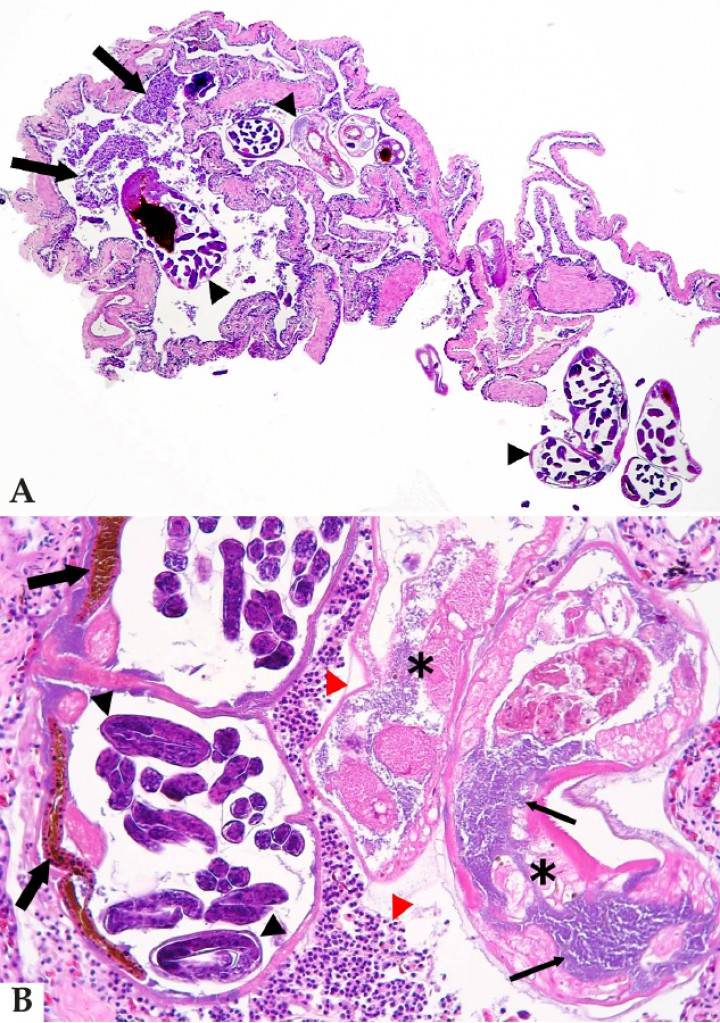

En cuanto a la nematodiasis de vías respiratorias, 7 anfibios mostraban nematodiasis pulmonar y 2 en la cavidad nasal. Los parásitos pulmonares correspondían a Rhabdias según la morfología característica de los nematodos, con presencia de un intestino cargado de pigmento marrón-amarillo (Fig. 8), útero con larvas rabditiformes en diversos estadios de desarrollo (Fig. 8B) y cuerdas laterales vacuolizadas. Las especies afectadas incluían 4 anuros (2 Scaphiophryne spp., 1 Dyscophus guineti y 1 Dendrobates tinctorius) y 3 tritones (Tylototriton spp.). En uno de estos animales, una rana globo de Madagascar (Scaphiophryne pustulosa), se observó un alto número de parásitos asociados a inflamación supurativa luminal (Fig. 8) relacionada con necrosis de algunos de los nematodos, que estaban colonizados por bacterias (Fig. 8B), así como zonas de infiltración intensa de la mucosa respiratoria por macrófagos alrededor de nematodos. En los 6 pacientes restantes no se apreció respuesta tisular a los nematodos. Dos anfibios, un dendrobátido y una mantella, mostraban nematodiasis en la cavidad nasal sin respuesta tisular salvo erosión y compresión de la mucosa nasal en la zona de contacto con los parásitos (Fig. 9).

<p>(<strong>A</strong>) Pulmón; rana globo de Madagascar (<em>Scaphiophryne pustulosa</em>). Imagen de bronconeumonía supurativa con exudado (flechas) asociado a la presencia de nematodos en la luz pulmonar (cabezas de flecha) característicos de <em>Rhabdias</em> por el pigmento marrón oscuro en la luz de su intestino y los úteros grávidos con larvas en desarrollo. Hematoxilina-eosina, x40. (<strong>B</strong>) Mismo caso que Fig. 8A. A mayor aumento, se observa el exudado purulento (cabezas de flecha rojas) alrededor de secciones de nematodos con pigmento marrón oscuro en la luz de su intestino (flechas gruesas) y los úteros grávidos con larvas en desarrollo (cabezas de flecha negras), característicos de <em>Rhabdias</em>. Dos de los nematodos están necróticos (asteriscos) y colonizados por abundantes bacterias (flechas delgadas). Hematoxilina-eosina, x400.</p>

(A) Pulmón; rana globo de Madagascar (Scaphiophryne pustulosa). Imagen de bronconeumonía supurativa con exudado (flechas) asociado a la presencia de nematodos en la luz pulmonar (cabezas de flecha) característicos de Rhabdias por el pigmento marrón oscuro en la luz de su intestino y los úteros grávidos con larvas en desarrollo. Hematoxilina-eosina, x40. (B) Mismo caso que Fig. 8A. A mayor aumento, se observa el exudado purulento (cabezas de flecha rojas) alrededor de secciones de nematodos con pigmento marrón oscuro en la luz de su intestino (flechas gruesas) y los úteros grávidos con larvas en desarrollo (cabezas de flecha negras), característicos de Rhabdias. Dos de los nematodos están necróticos (asteriscos) y colonizados por abundantes bacterias (flechas delgadas). Hematoxilina-eosina, x400.